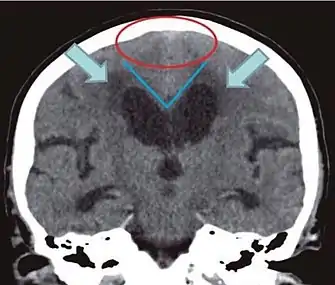

• Imaging from magnetic resonance imaging (MRI) or computed tomography (CT) is needed to demonstrate enlarged ventricles and no macroscopic obstruction to cerebrospinal fluid flow. Imaging should show an enlargement to at least one of the temporal horns of lateral ventricles, and impingement against the falx cerebri resulting in a callosal angle ≤ 90° on the coronal view, showing evidence of altered brain water content, or normal active flow (which is referred to as "flow void") at the cerebral aqueduct and fourth ventricle.

Typical imaging findings in normal pressure hydrocephalus versus brain atrophy.[9]

Normal pressure hydrocephalusBrain atrophy

Preferable projectionCoronal plane at the level of the posterior commissure of the brain.

Modality in this exampleCTMRI

CSF spaces over the convexity near the vertex (red ellipse )Narrowed convexity ("tight convexity") as well as medial cisternsWidened vertex (red arrow) and medial cisterns (green arrow)

Callosal angle (blue V)Acute angleObtuse angle

Most likely cause of leucoaraiosis (periventricular signal alterations, blue arrows ) Transependymal cerebrospinal fluid diapedesis Vascular encephalopathy, in this case suggested by unilateral occurrence